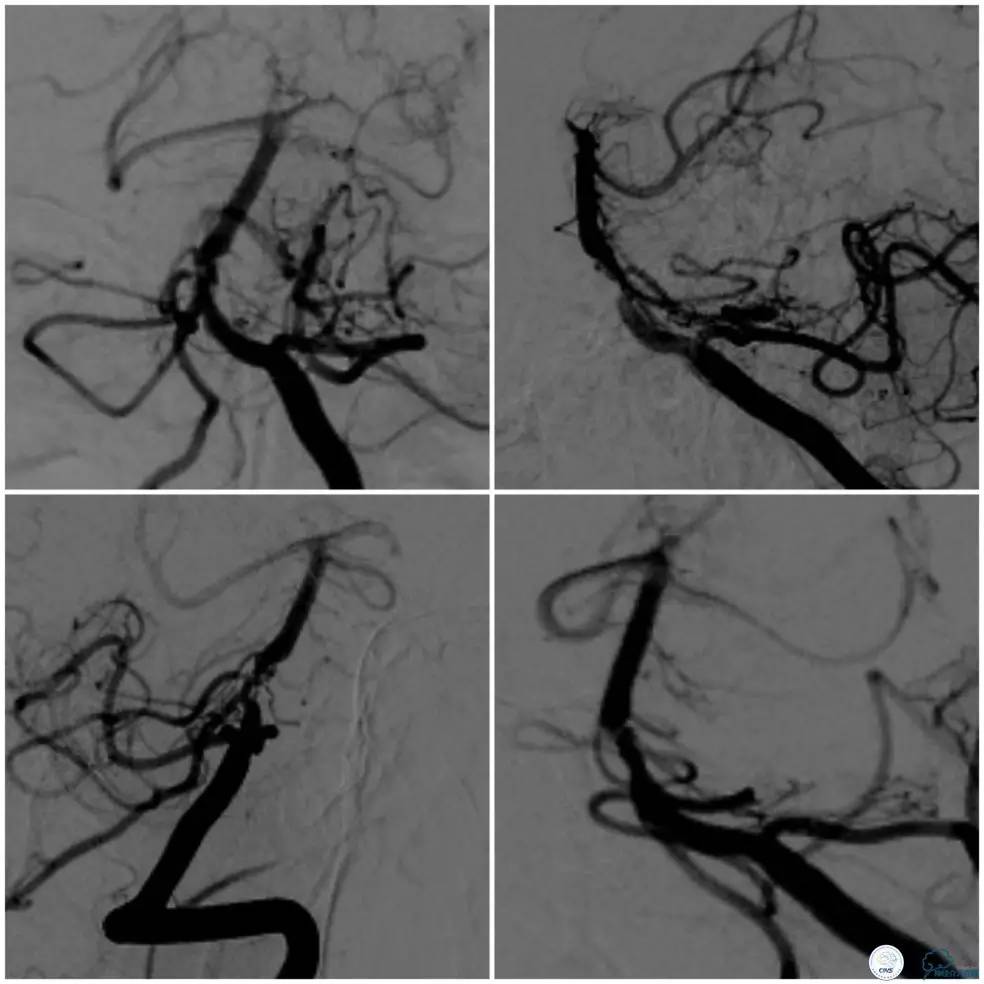

颅内动脉粥样硬化性狭窄多为偏心性狭窄分布于管腔某一壁。但我们也可见突出于管腔内的狭窄,造影显示狭窄轮廓不清,某些投造体位可见充盈缺损(图1,来自秦皇岛市第一医院,杨大为主任提供),类似“蜂巢样”改变,或者呈“夹层样”改变。本周我们汇报病例系一例基底动脉“蜂巢样”狭窄支架治疗的过程。

术前造影(图5、6):基底动脉近段狭窄,局部管腔不规则,似有“充盈缺损样改变”,管壁不光滑,前向血流减慢。可见右后交通动脉开放,见双侧大脑后动脉,基底动脉尖和上段显影。

图5

图6